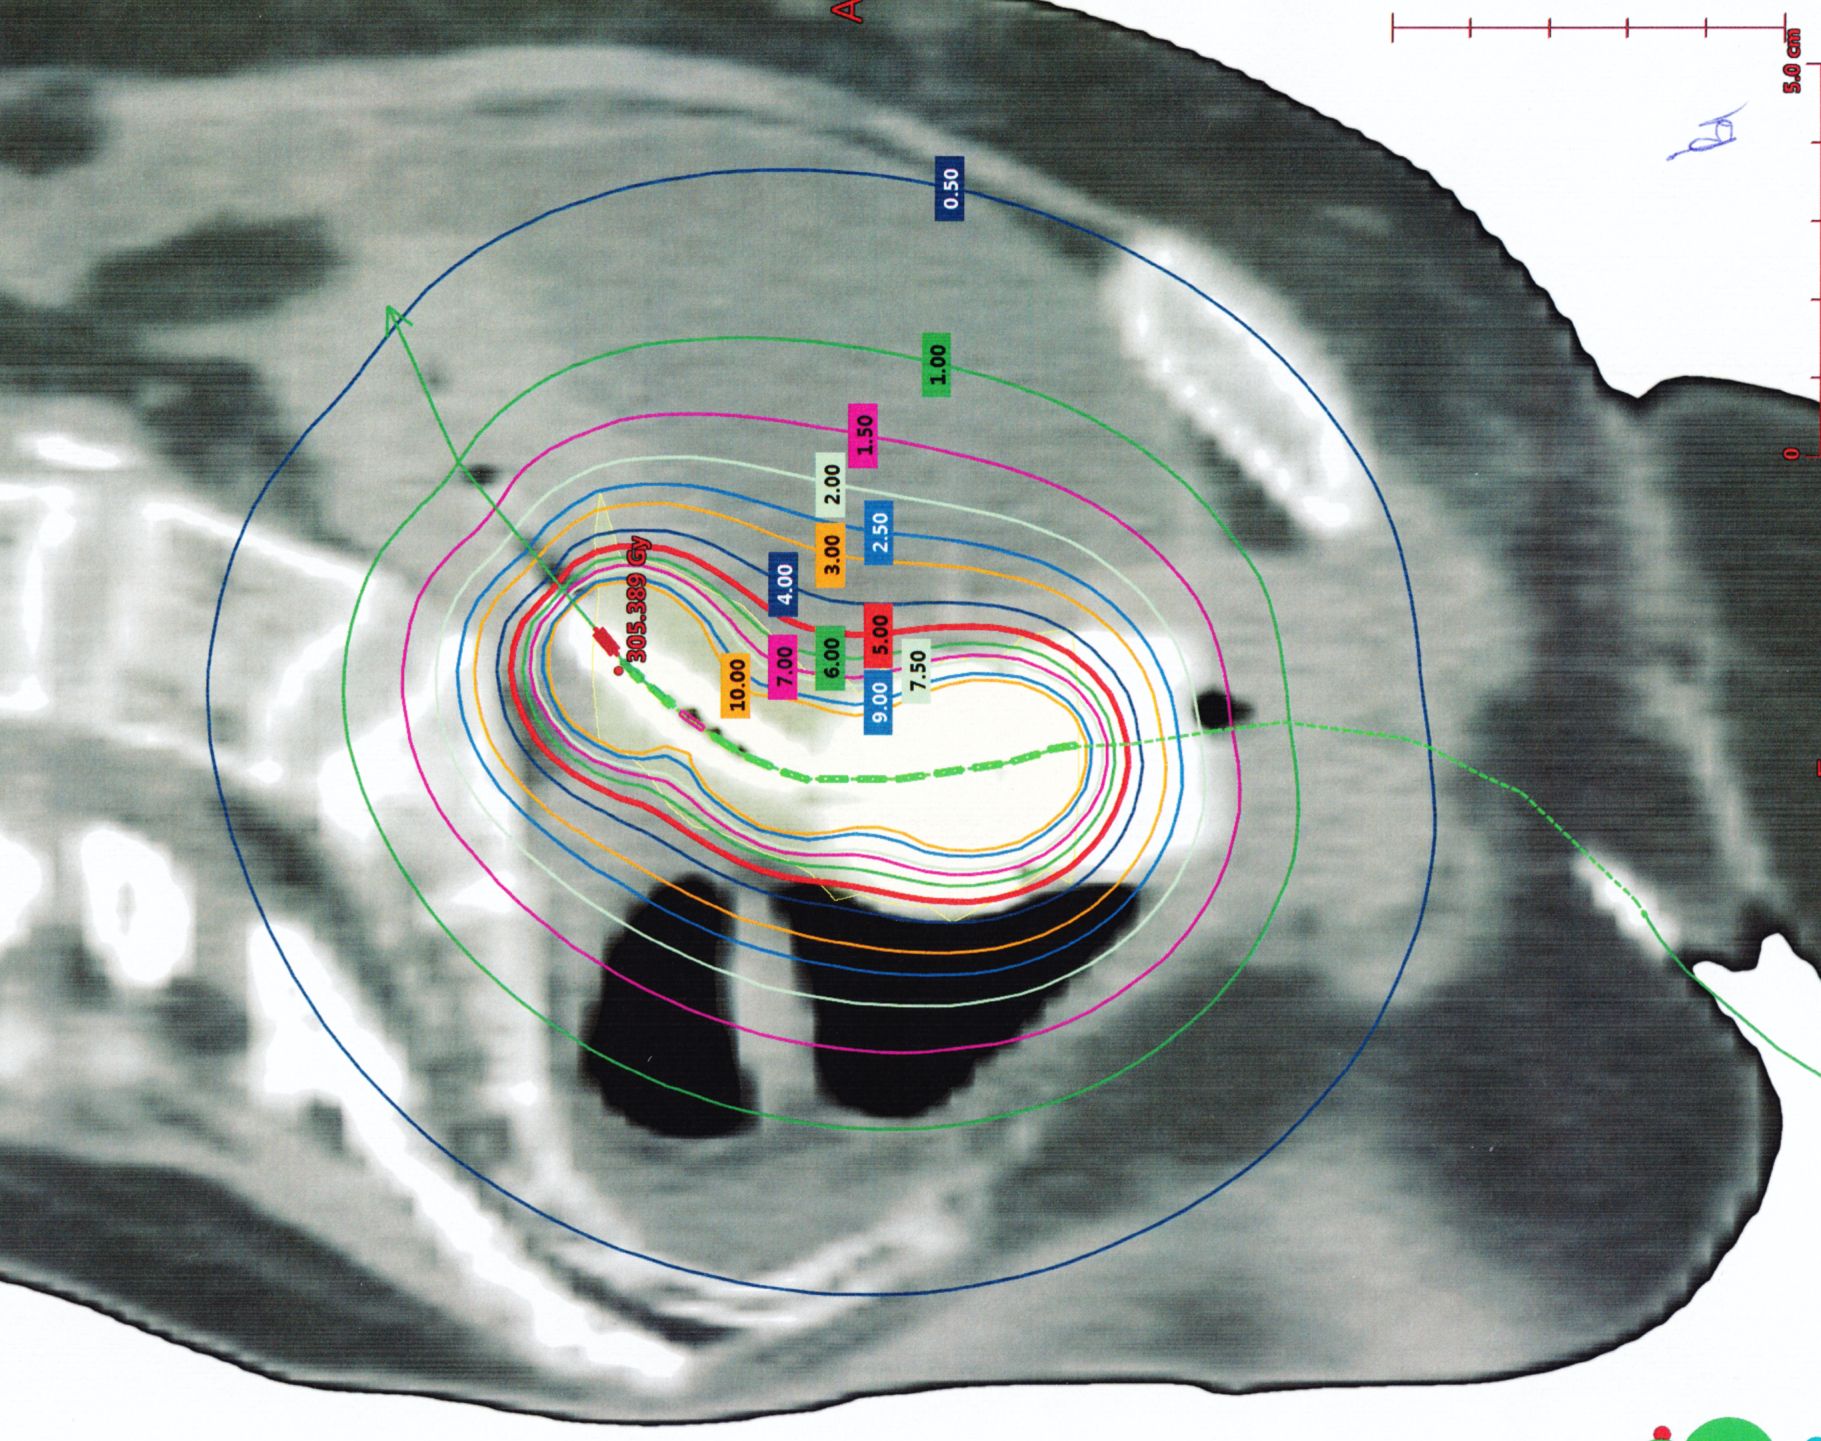

CT mit liegender Intrauterinsonde und überlagerten Isodosen.![]() | ||||